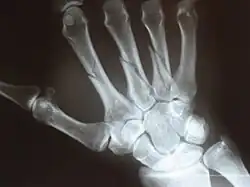

X-ray

X-ray image of right hand with thumb on left. -

Multiple fractures of the metacarpals (aka broken hand). (Right hand shown with thumb on left.) -